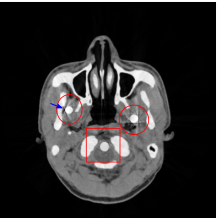

The proposed re-weighted JSR model requires a pre-estimation of the metal trace and weights in projection domain. They can be obtained fairly easily from a roughly reconstructed CT image using a simple reconstruction model. In this paper, we use the tight wavelet frame based analysis model [8]. This subsection describes the details on how metal trace and weights are computed using the NURBS-based cardiac-torso(NCAT) phantom [45]. Two metal components are implanted in the NCAT phantom as shown in Figure 1(a) and the simulated projection data is obtained from a multi-chromatic X-ray source. Details on the settings of the imaging system are postponed to Section 4.1.1.

The optimization problem (2.12) can be solved by the split Bregman algorithm [29, 8] efficiently, which is also equivalent to the alternating direction method of multipliers (ADMM) [24, 26, 28]. The reconstructed phantom image by model (2.12), denoted by , is shown in Figure 1(b). Metal location in image domain can be robustly estimated by the summation of the high frequency wavelet frame coefficients (Figure 1(c)) followed by a simple thresholding. Then, the index of the metal trace in Radon domain, denoted by , can be identified by the projection of the indicator function associated to the metal location (Figure 1(d)).

The NCAT phantom (shown in Figure 1(a)) and the cerebral phantom111http://see.xidian.edu.cn/vipsl/database_CTMR.html (shown in Figure 8(a)) are chosen as image phantoms. For the NCAT phantom, it has pixels. Two metal components (Titanium) are implanted in the image, which is shown in Figure 1(a) with red curves labeling the locations of the metals. For the cerebral phantom, it has pixels and three metal components (Titanium) are implanted. Both of the phantoms contain three major components, i.e. soft tissue, bone and metal components, and their linear attenuation coefficients can be found in [30].

Figure 7(a) shows that the reconstructed NCAT phantom from FBP has severe metal artifacts and is noisy. The reconstructed image from the unweighted JSR model (3.2) shown in Figure 7(b) has a better visual effect with noticeably less noise and metal artifacts. Sharp edges are also well preserved except for the blurry effects in the region surrounding the metals. The reconstructed image from NMAR shown in Figure 7(c) also has most of the metal artifacts suppressed and the regions surrounding the metals are much less blurry than the unweighted JSR. However, the unweighted JSR does a better job than NMAR in suppressing noise and preserving sharp image features away from the metals. TV-FADM is able to reconstruct images with minimum metal artifacts and noise, as shown in Figure 7(d). However, the metal components are fused with nearby structures which is highlighted by the red arrow. The reconstructed image from proposed re-weighted JSR model has the best overall quality with rather minor metal artifacts.

Figure 8 shows the reconstructed cerebral phantom from different methods. We highlight some regions with more distinct differences with red contours. Since the cerebral phantom contains more textures, it is more challenging than the NCAT phantom. The pros and cons of these methods are mostly the same as the previous example. However, we note that the reconstructed image from TV-FADM shown in Figure 8(e) has severe artifact, which is due to the well-known staircase artifact of TV regularization. We found that TV-FADM is relatively sensitive to the choice of its parameters. It is not easy to balance between sharpness of image features and metal artifacts reduction. The soft tissue around metal components is also not well preserved by the NMAR method as indicated by the blue arrow in Figure 8(d). Furthermore, the circled areas in Figure 8(d) show that there are still some artifacts around the metal. Same as the NCAT phantom, the proposed re-weighted JSR model has the best overall performance. Notice that the intensity of metals in Figure 8(d) and 8(f) seems lower than the rest of the reconstructed images. This is because we set the intensity of the metal components in the segmentation with the same mean value as that of bones. Increasing the value of metal components of can increase the intensity of metals in the reconstructed images, whereas it also introduces more artifacts around the metals.